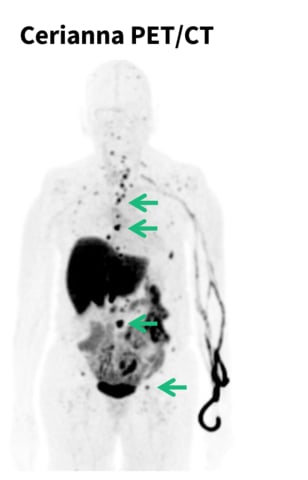

The NCCN Guidelines now recommend the use of fluoroestradiol PET imaging for systemic staging in patients with invasive lobular breast cancer, following an update from GE HealthCare regarding its imaging agent, Cerianna (fluoroestradiol F18). This recommendation aims to enhance diagnostic accuracy and early intervention for recurrent or metastatic lobular breast cancer, which is often difficult to detect. Cerianna is the only FDA-approved imaging agent for assessing estrogen receptor positive lesions, making it a valuable tool in a clinical setting. The guidelines, established by an expert working group, emphasize the importance of PET imaging in diagnosing this hard-to-detect cancer type, potentially improving insurance coverage and aligned clinical decisions.